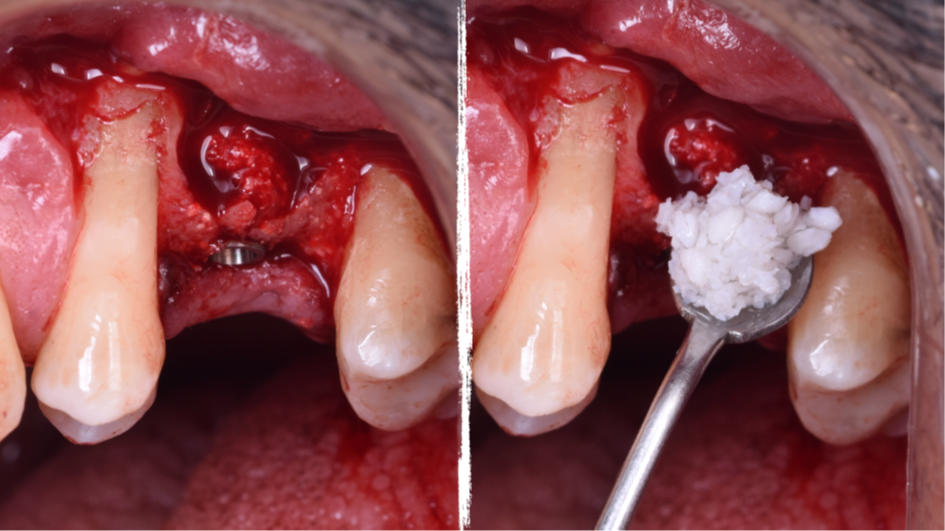

O presente trabalho tem como objetivo fazer um relato de caso clínico de reintervenção em enxerto ósseo para levantamento de seio maxilar pela técnica da janela lateral com instalação simultânea de implante Maestro Superiore.